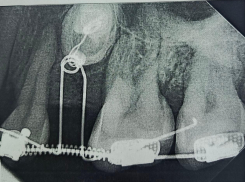

- Общество Взрослой пациентке вернули на место непрорезавшиеся зубы в Воронеже 30.01.2026